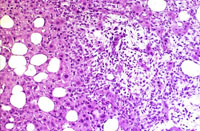

This Ito cell tumor is comprised of a mixture of stellate cells and mature adipocytes.